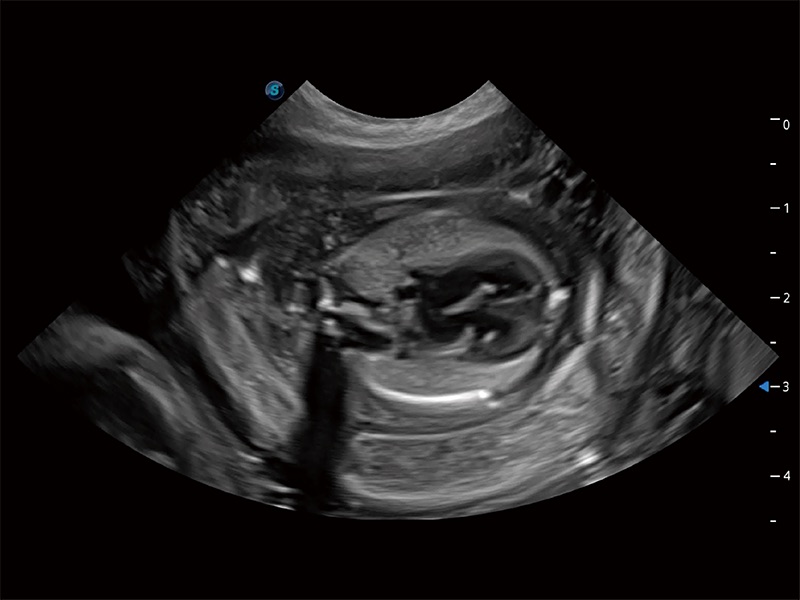

动物是人类最亲密的朋友和最值得信赖的伙伴。银河优越会也一直致力于探索动物专用的超声影像解决方案。全新推出的ProPet系列,是银河优越会在动物超声影像智能化、专业化、精准化的一次跨越式革新。动物不能用言语来表述自己的不适,通过超声影像,ProPet系列搭建了动物医生与不同物种沟通的“桥梁”,为动物医生注入了“治愈之力”。 ProPet 80 是银河优越会匠心打造的一款高端动物专用彩超,采用性能卓越的全新硬件架构,极大提升超声系统的运行效率和数据处理能力,帮助动物医生从容应对日益增多的挑战性病例和日益多样化的临床需求。

高性能和先进的临床应用工具可以为动物医生提供临床信心。ProPet 80 搭载了先进的腹部和浅表应用工具,帮助医生在日常临床实践中发挥前所未有的作用。

ProPet 80 专为动物医生设计,对不同的动物体型和生理结构作出了针对性的优化。通过动物影像专用软件,可满足个性化的应用需求,帮助动物医生获得更精确的诊断数据。